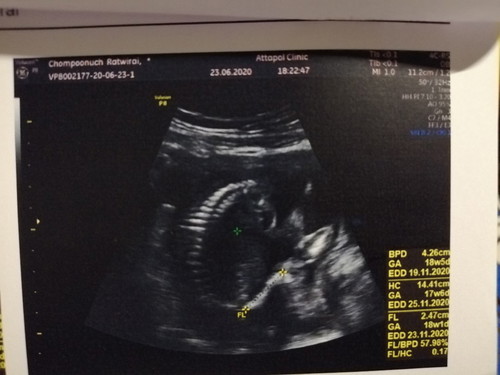

พอดีว่าตอนไปฝากครรภ์หมอบอกเรา20สัปดาห์2วันค่ะ แต่ไปซาวมา หมอบอกว่าตน้องได้18สัปดาห์3วันค่ะ แต่เราลูกอยู่ต่ำจะเป็นไรไหมคะ เพราะหมอไม่ได้ว่าอะไร แค่บอกเด็กนอนหดตัวอยู่ข้างล่าง เลยไม่รู้เพศ

ถ้าจำ ปจด. ไม่ได้ ก็ยึกตามใบซาวด์ครั้งแรกค่ะ อาจจะคลาดเคลื่อนนิดหน่อย

ถ้าอายุครรภ์น้อย น้องจะอยู่ต่ำค่ะ